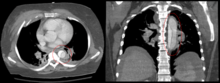

CT with contrast demonstrating aneurysmal dilation and a dissection of the ascending aorta (type A Stanford)

Chest CT with descending (type B Stanford) aortic dissection (red circle)

Computed tomography angiography is a fast, noninvasive test that gives an accurate three-dimensional view of the aorta. These images are produced by taking rapid, thin-cut slices of the chest and abdomen, and combining them in the computer to create cross-sectional slices. To delineate the aorta to the accuracy necessary to make the proper diagnosis, an iodinated contrast material is injected into a peripheral vein. Contrast is injected and the scan performed using a bolus tracking method. This type of scan is timed to an injection to capture the contrast as it enters the aorta. The scan then follows the contrast as it flows though the vessel. It has a sensitivity of 96 to 100% and a specificity of 96 to 100%. Disadvantages include the need for iodinated contrast material and the inability to diagnose the site of the intimal tear.